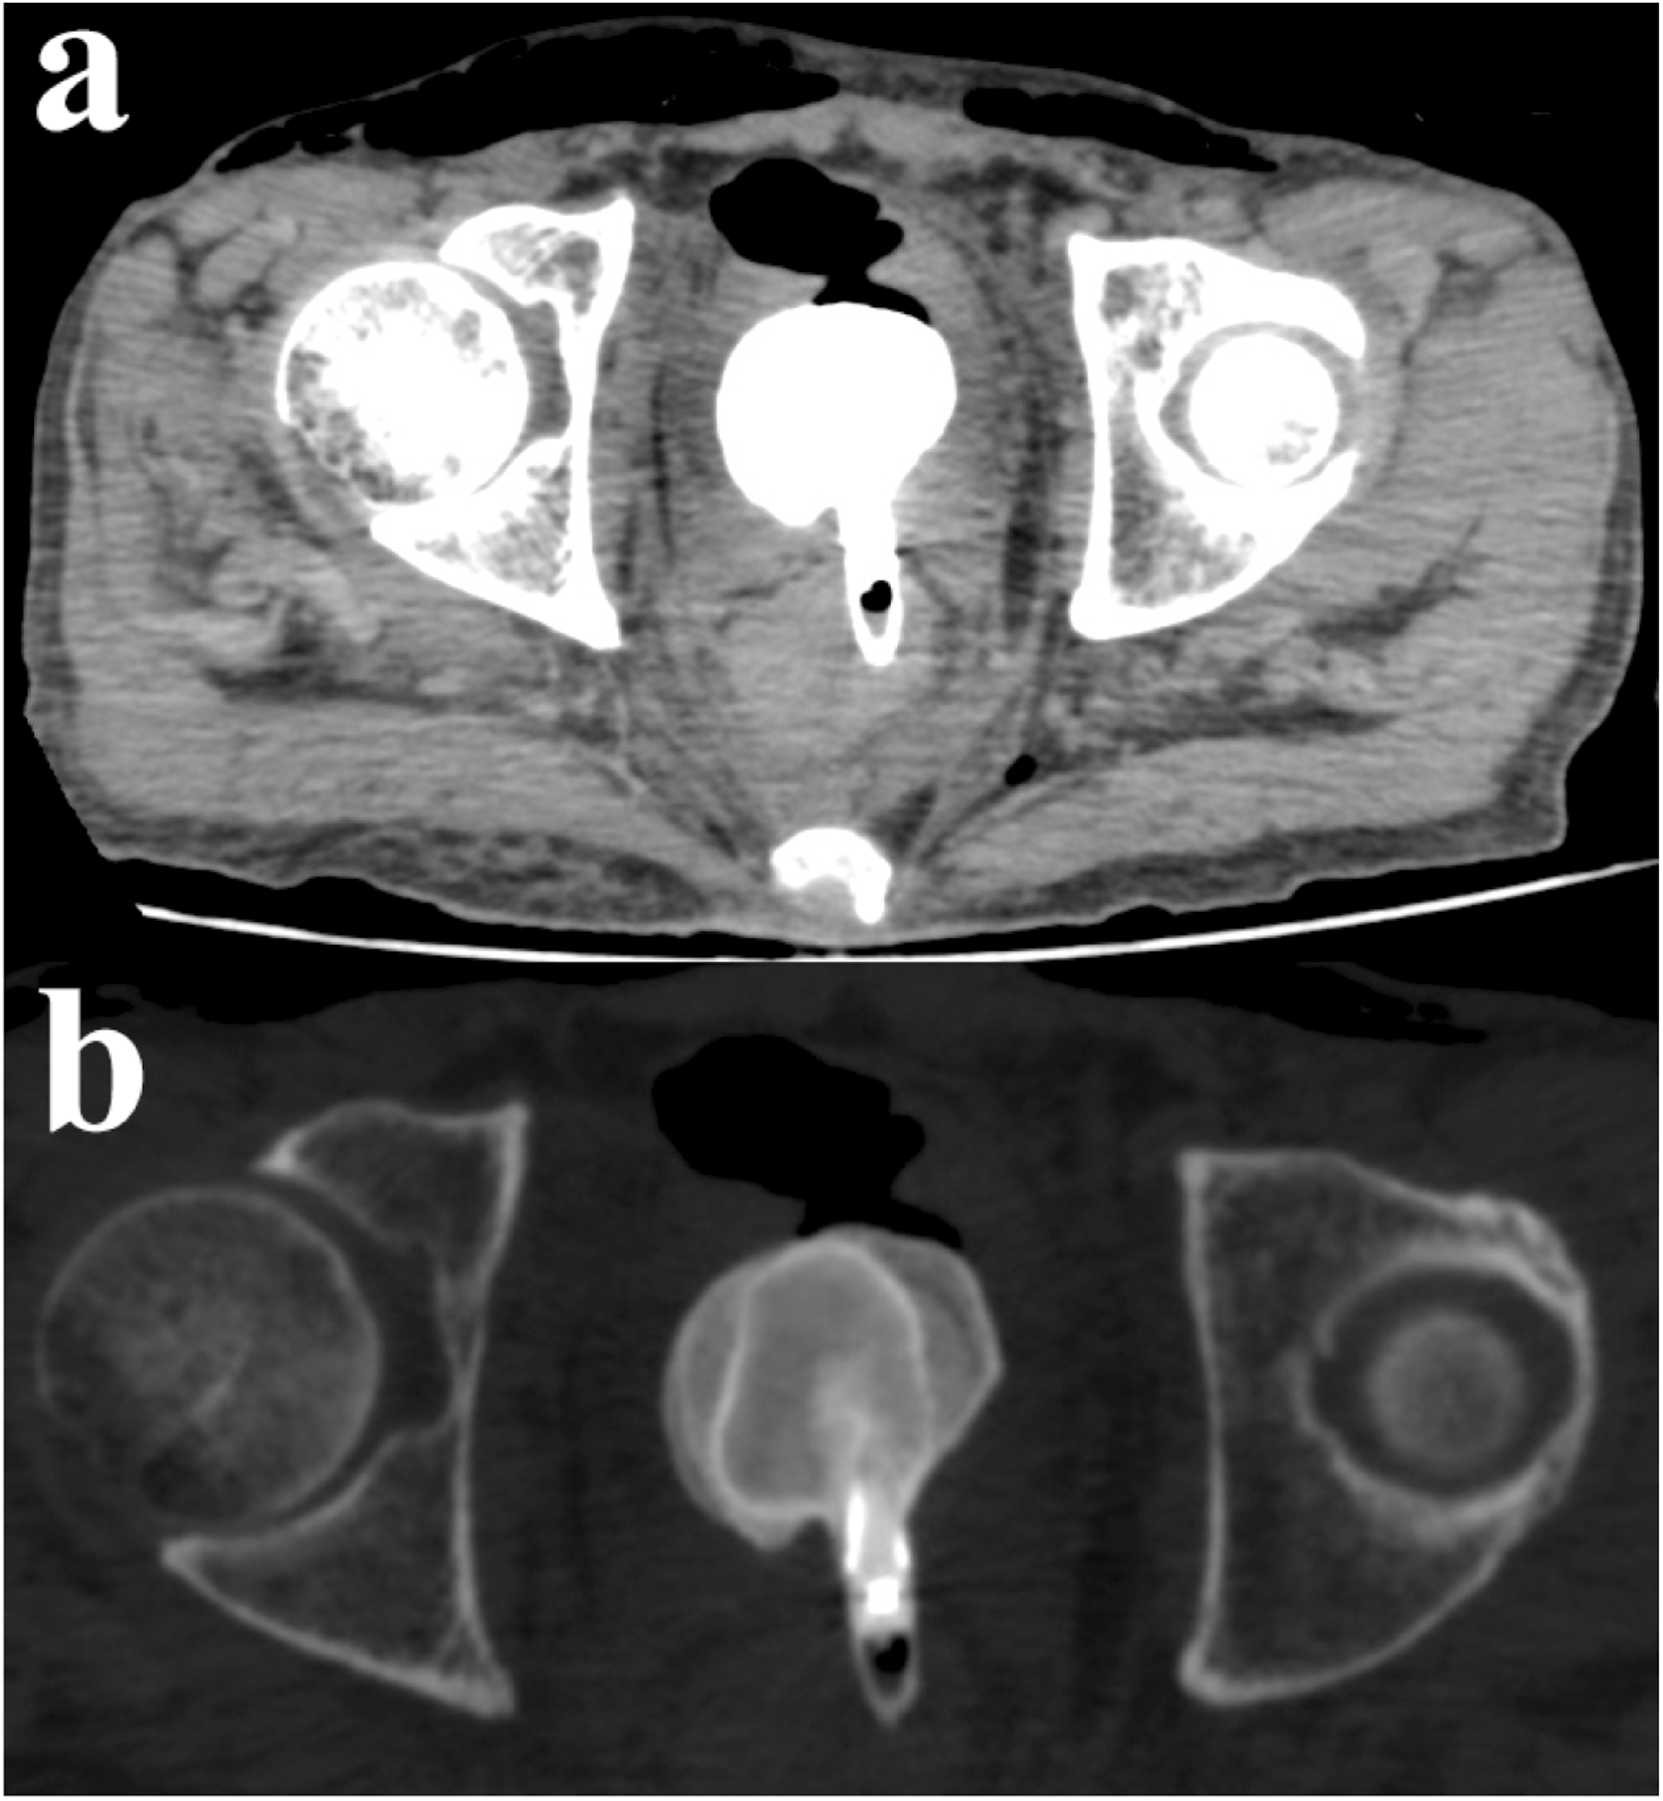

A hatvanas éveiben járó férfi három éve szenvedett visszatérő hasi fájdalomtól. Két héttel halála előtt étvágytalanságra és hasmenésre panaszkodott. Miután elájult, kórházba szállították, ahol az orvosok két napig sikertelenül küzdöttek az életéért. A CT-vizsgálat ugyanakkor egy idegen tárgyat mutatott ki a végbelében. A tárgy pontos természetére csak a halála utáni boncolás során derült fény: A ScienceDirect jelentése szerint egy megdöbbent igazságügyi patológus egy alumínium szemceruzát talált az elhunyt férfi végbelében.

A 9 centiméteres ceruza körül egy hatalmas, 6,5 cm x 6 cm x 4 cm-es hólyagkő képződött.

Fotó: sciencedirect.com/Forensic Science International: Reports/article/pii/S2665910724000343